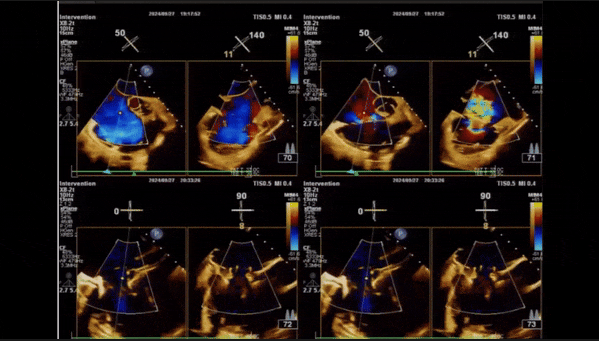

術(shù)前TEE評估

1、3D TEE顯示雙房及右室擴(kuò)大,右室中段直徑40mm,右室FCA 52%。三尖瓣環(huán)TAPSE 22mm,三尖瓣環(huán)左右徑49mm,三尖瓣隔葉長度16mm,前葉長度21mm,后葉長度34mm,三尖瓣前隔gap 11mm,后隔gap 5.6mm,AP gap 12mm,診斷極重度功能性三尖瓣返流(Type I型三尖瓣:Torrential FTR 5+)。

2、彩色多普勒顯示:收縮期三尖瓣口返流束起源于后隔交界、前后葉之間及前隔交界,返流束縮流頸最大寬度27mm,三尖瓣返流口EOA=2.02cm2,返流容積124ml,收縮期三尖瓣返流峰值速度2.64m/s,返流峰值壓差28mmHg,PAPs 43mmHg,舒張期三尖瓣口平均跨瓣壓差1mmHg,肝左靜脈可見明顯逆向血流波。